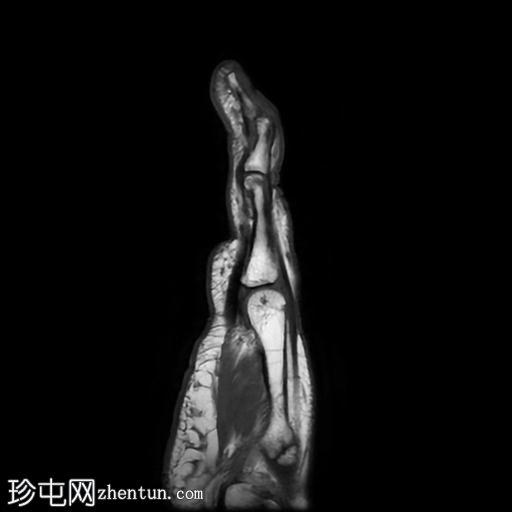

MRI

矢状位

T1加权像

PD脂肪抑制像

第五指小指伸肌腱远端纤维完全撕裂,伴远端指间关节屈曲畸形。

撕裂肌腱近端位于第五指中节指骨头附近,止点与近端撕裂处之间约有4毫米的间隙。

患者左手受伤,导致第五指小指伸肌腱远端止点纤维完全撕裂,并伴有槌状指畸形。